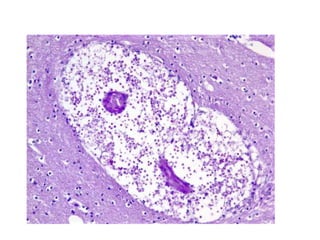

• #34 Cryptococci in perivascular space

• #35 Mucicarmine

• #36 Alcian Blue

• #37 PAS

Case 4 • 32year old male • K/C/O- Retroviral disease • C/O- fever, headache x 3 days • A/w- Confusion, forgetfullness • O/E – Moderate grade fever, cranial nerves normal • Minimal nuchal rigidity, hyperreflexic • CSF- high TLC , lymphocyte predominant • India Ink - Positive